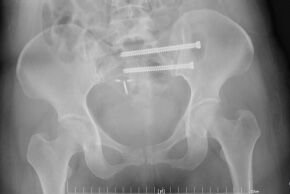

微创通道螺钉手术就是用一根或几根长度不同的空心螺钉将骨折处复位,由于盆骨周围血管密布,失之毫厘就会差之千里,医生谨慎地完成了严密的术前设计,确定入口位和进钉点,以及置入通道。保证医用螺钉精准无误置入骨盆,避免角度不对损伤神经,术中在“铅衣”保护下通过C型臂X光机反复透视,术中切开1cm的切口,通过切口将骶髂螺钉S1、S2两根空心螺钉对骨折部位进行内固定,经过两个小时的努力,手术顺利完成。